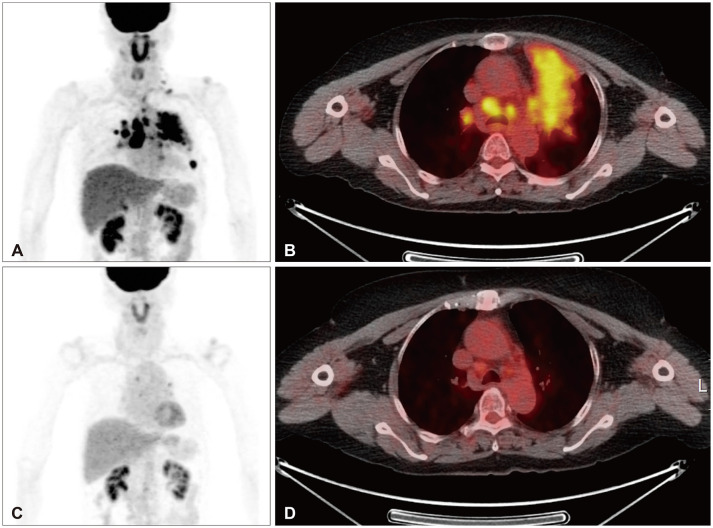

We report complete remission of dural-based leptomeningeal metastasis (LM) in an 80-year-old female patient with non-small cell lung cancer (NSCLC) by osimertinib. She was diagnosed with NSCLC (adenocarcinoma, T4N3M1a) 8 years ago. Mutation analysis of biopsied tissue revealed exon 19 deletion positive, and gefitinib was prescribed. Follow-up chest CT showed a radiological response, and whole-body positron emission tomography 3 years later revealed the disappearance of the previous high-uptake lesions. The medication was continued for maintenance but stopped 4 years later due to intolerable dermatitis. Two years after discontinuing chemotherapy, the patient had a gait disturbance, and brain MRI revealed a right cerebellar mass (diameter [d]=3 cm) with peritumoral edema, compatible with solitary brain metastasis. Retromastoid suboccipital craniotomy and gross total removal of the dura-attached lesion were performed. As the systemic cancer status evaluation revealed no radiological cancer lesion, only tumor bed radiation therapy was given (4,000 cGy/10 fractions) without re-introducing gefitinib. She was followed with a brain MRI at 6-month intervals, and a brain MRI 2 years postoperatively revealed a dural-based extra-axial mass in the left prepontine cistern (d=2.2 cm). Serial cerebrospinal fluid (CSF) cytology was positive for cancer cells. Upon LM diagnosis, the third-generation receptor tyrosine kinase inhibitor osimertinib was given. Two-month follow-up CSF cytology and five consecutive tests over 14 months demonstrated negative conversion. Five-month follow-up brain MRI revealed near complete remission of dural-based LM, and the response was maintained until the 13-month follow-up brain MRI.

我们报告了一位80岁的女性非小细胞肺癌(NSCLC)患者通过奥希替尼治疗硬脑膜脑膜转移(LM)完全缓解的病例。她在 8 年前被诊断为非小细胞肺癌(腺癌,T4N3M1a)。活检组织的突变分析显示 19 号外显子缺失为阳性,医生给她开了吉非替尼。随访的胸部 CT 显示有放射反应,3 年后的全身正电子发射断层扫描显示之前的高吸收病灶消失了。患者继续接受药物维持治疗,但 4 年后因无法忍受皮炎而停药。停止化疗两年后,患者出现步态障碍,脑部核磁共振检查发现右侧小脑肿块(直径[d]=3厘米),瘤周水肿,符合单发脑转移。患者接受了后枕骨下开颅手术,彻底切除了硬膜外病灶。由于全身癌症状况评估未发现放射性癌症病灶,因此只进行了肿瘤床放疗(4,000 cGy/10次分次),未再次使用吉非替尼。术后两年的脑部核磁共振检查显示,左侧桥脑前囊有硬膜外肿块(d=2.2 厘米)。连续的脑脊液(CSF)细胞学检查显示癌细胞阳性。LM确诊后,患者接受了第三代受体酪氨酸激酶抑制剂osimertinib治疗。两个月的CSF细胞学随访和14个月的连续五次检测均显示阴性。五个月的脑磁共振随访显示,硬脑膜LM几乎完全缓解,这种反应一直维持到13个月的脑磁共振随访。